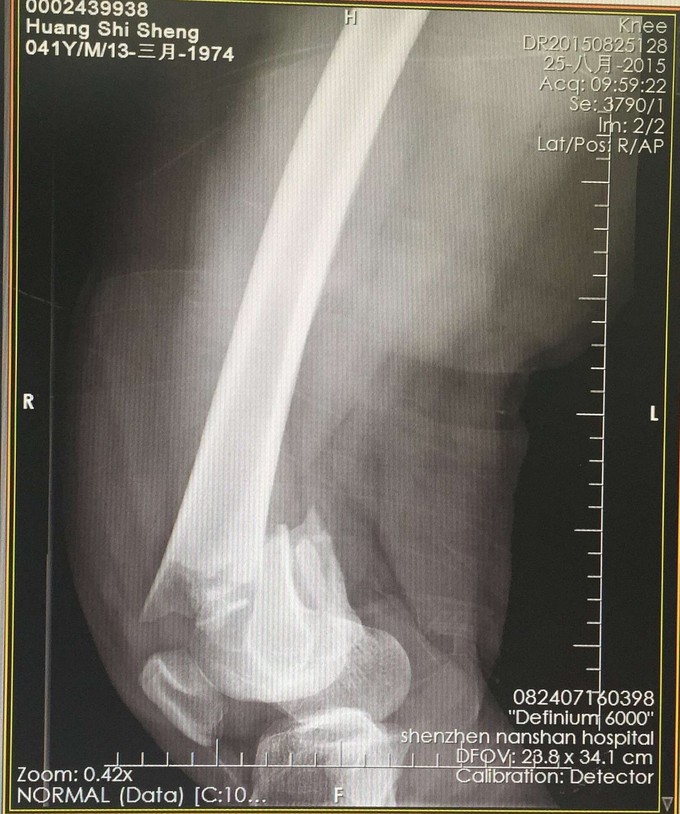

股骨远端粉碎骨折

查体:右大腿中下段短缩成角畸形,肿胀,可扪及骨擦感,患肢末梢感觉血运可。 X:右股骨下端骨折 CT:右股骨下端骨折,波及关节面。

右股骨远端粉碎性骨折 完善检查,行右股骨远端骨折切开复位内固定术。